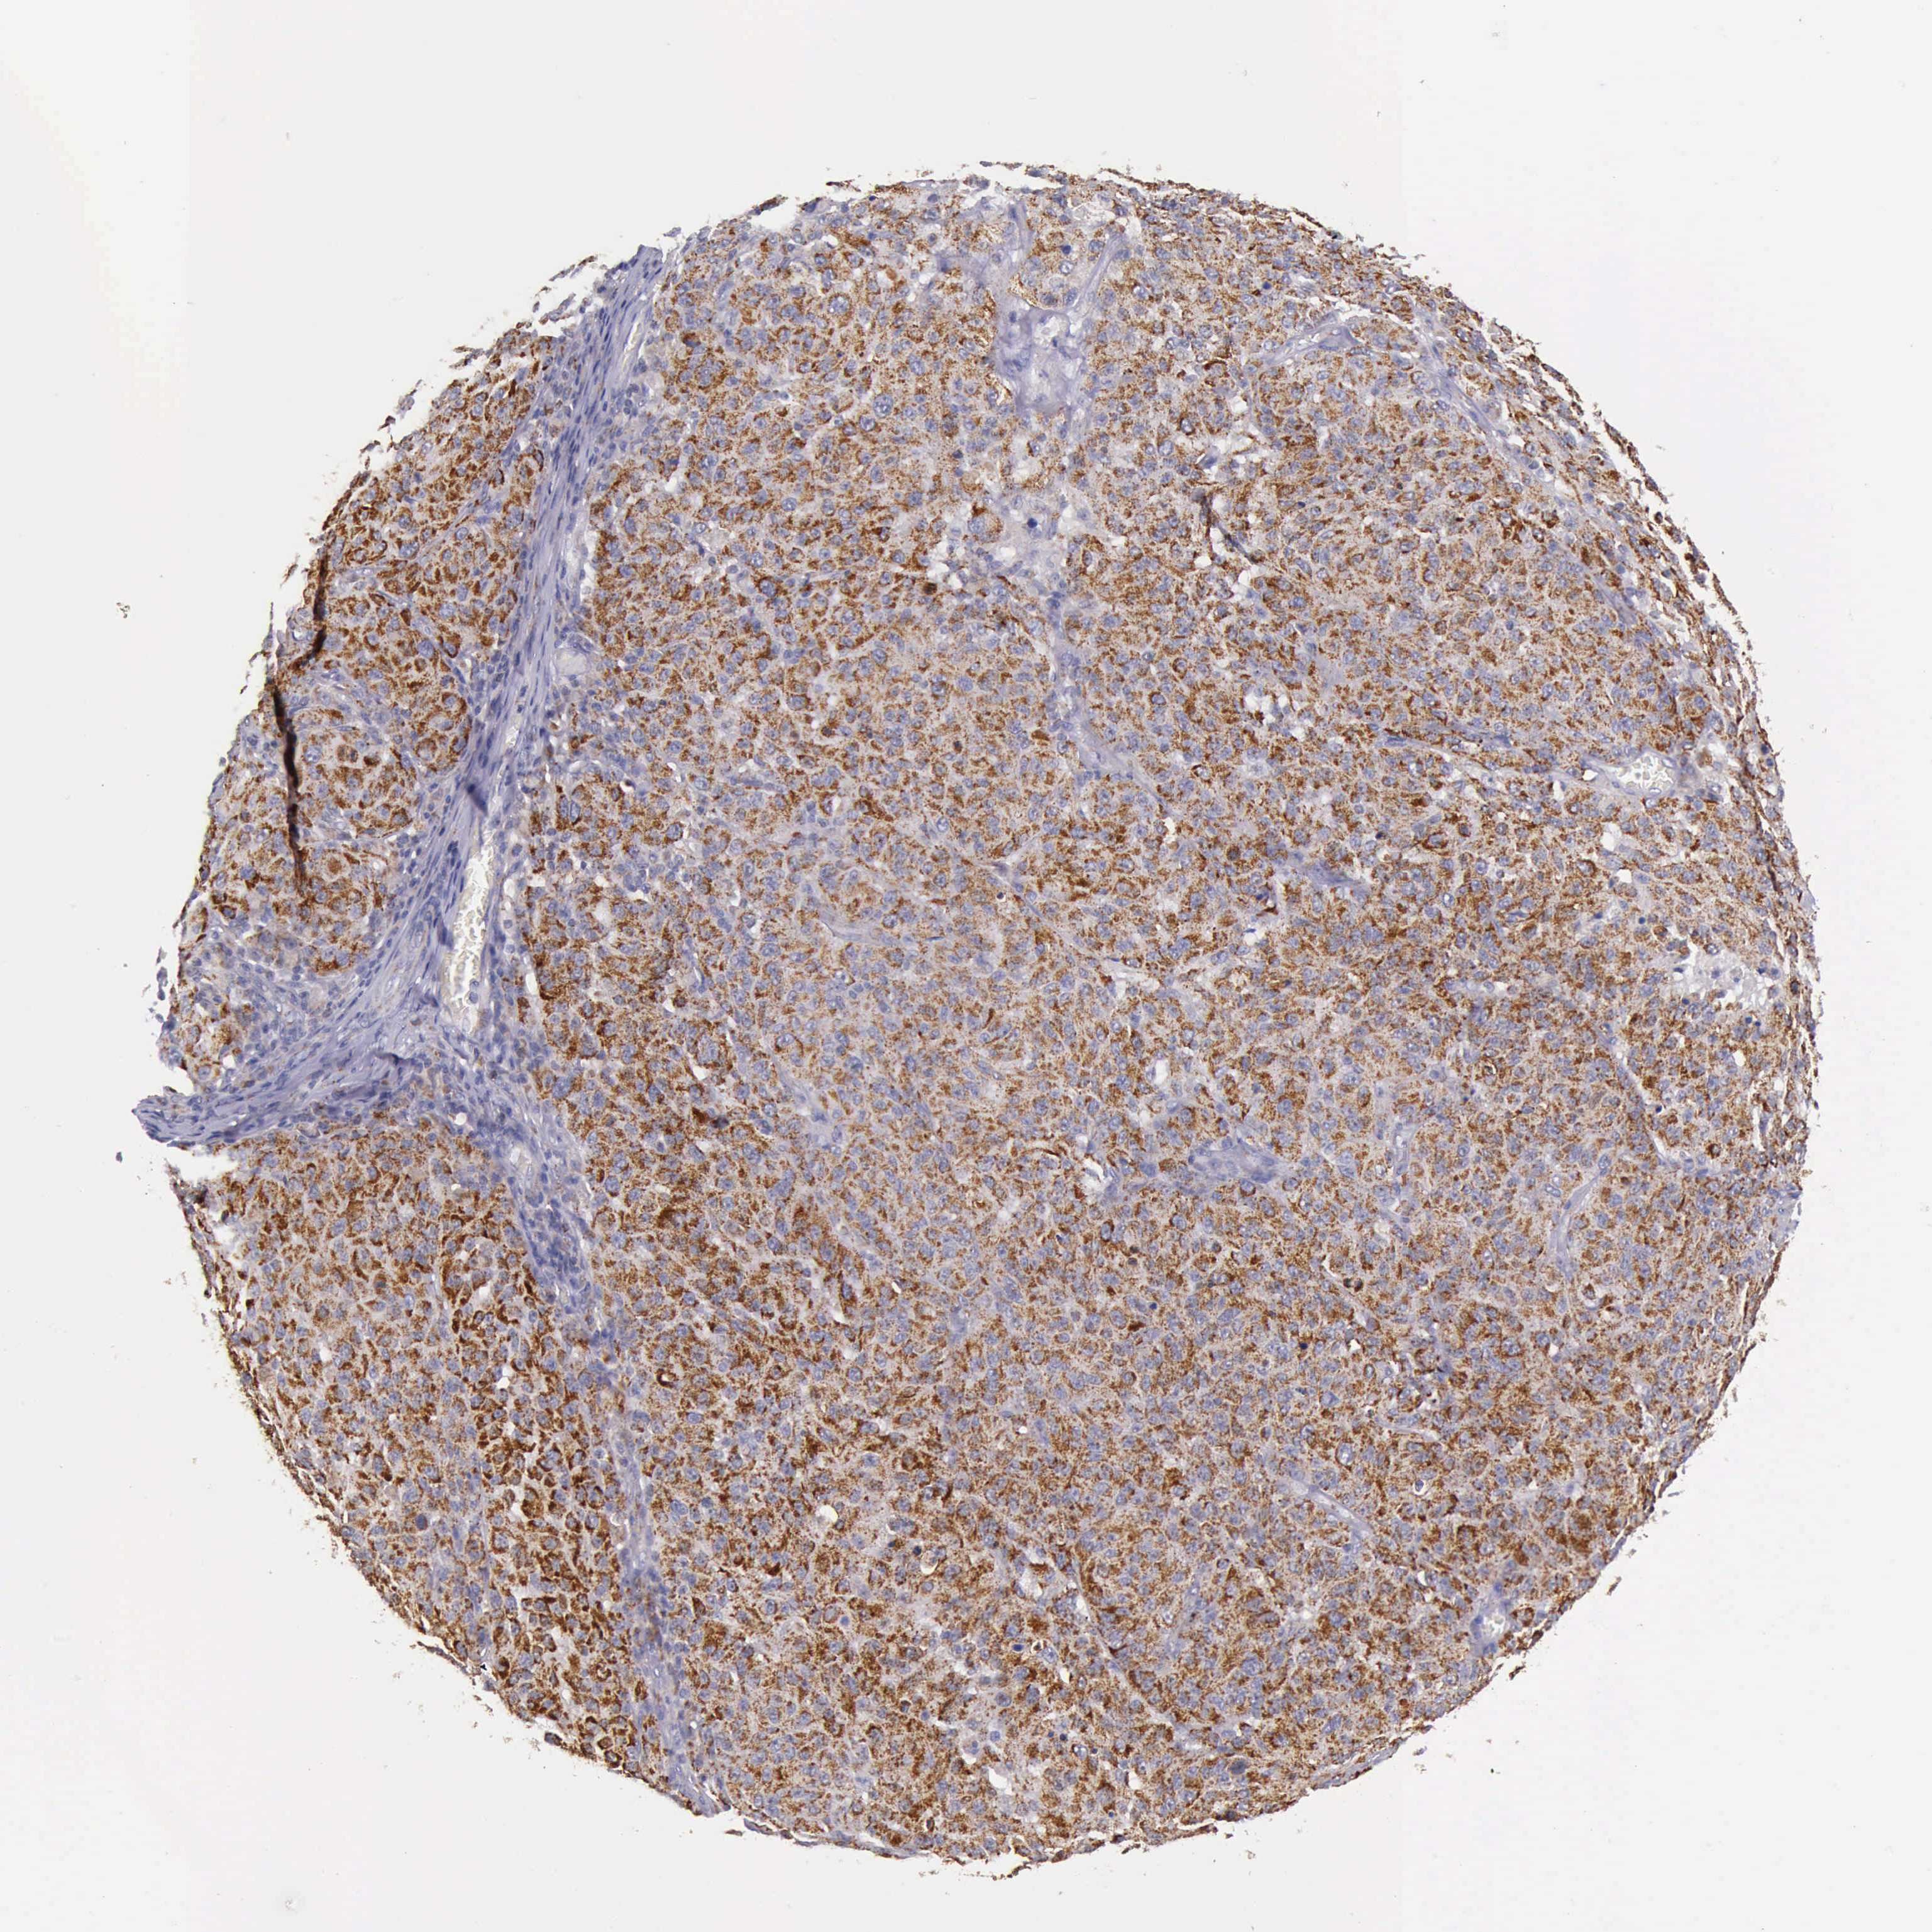

MELANOMA - Protein expressioni

A mouse-over function shows sample information and annotation data. Click on an image to view it in a full screen mode. Samples can be filtered based on level of antibody staining by selecting one or several of the following categories: high, medium, low and not detected. The assay and annotation is described here.

Note that samples used for immunohistochemistry by the Human Protein Atlas do not correspond to samples in the TCGA dataset.

Antibody stainingi

Antibody staining in the annotated cell types in the current human tissue is reported as not detected, low, medium, or high, based on conventional immunohistochemistry profiling in selected tissues. This score is based on the combination of the staining intensity and fraction of stained cells.

Each image is clickable and will lead to virtual microscopy that enables deeper exploration of all samples and also displays staining intensity scores, fraction scores and subcellular localization as well as patient and tissue information for each sample.

Antibody HPA000994

Antibody CAB008681

Staining

High

Medium

Low

Not detected

Intensity

Strong

Moderate

Weak

Negative

Quantity

>75%

75%-25%

<25%

None

Location

Nuclear

Cytoplasmic/membranous

Cytoplasmic/membranous,nuclear

Malignant melanoma, NOS

Malignant melanoma, Metastatic site